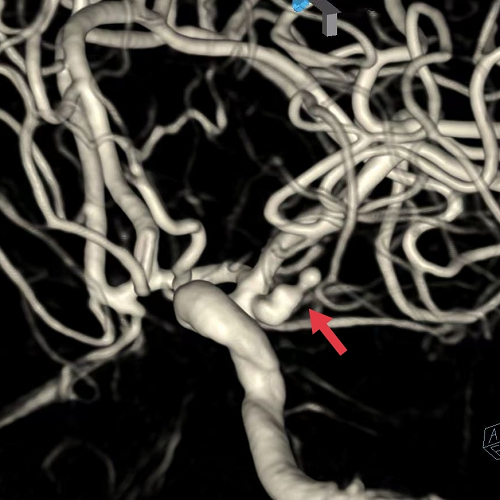

术中三维造影显示左侧不规则后交通动脉瘤,顶端可见子瘤,约3.3*8mm,手术难度及风险相当大。脑血管病介入团队采取了双微导管交替栓塞技术,经过2个小时的手术,患者这颗颅内“不定时炸弹”被成功拆除。过程顺利,动脉瘤达到致密栓塞,载瘤动脉及后交通动脉通畅。术后患者转入ICU接受术后治疗。

▲3D-DSA显示不规则后交通动脉瘤,顶端有子瘤